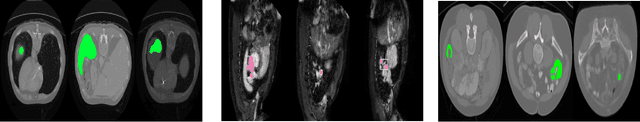

Abstract:The last decade of computer vision has been dominated by Deep Learning architectures, thanks to their unparalleled success. Their performance, however, often comes at the cost of explainability owing to their highly non-linear nature. Consequently, a parallel field of eXplainable Artificial Intelligence (XAI) has developed with the aim of generating insights regarding the decision making process of deep learning models. An important problem in XAI is that of the generation of saliency maps. These are regions in an input image which contributed most towards the model's final decision. Most work in this regard, however, has been focused on image classification, and image segmentation - despite being a ubiquitous task - has not received the same attention. In the present work, we propose MiSuRe (Minimally Sufficient Region) as an algorithm to generate saliency maps for image segmentation. The goal of the saliency maps generated by MiSuRe is to get rid of irrelevant regions, and only highlight those regions in the input image which are crucial to the image segmentation decision. We perform our analysis on 3 datasets: Triangle (artificially constructed), COCO-2017 (natural images), and the Synapse multi-organ (medical images). Additionally, we identify a potential usecase of these post-hoc saliency maps in order to perform post-hoc reliability of the segmentation model.

Abstract:Today, deep convolutional neural networks (CNNs) have demonstrated state-of-the-art performance for medical image segmentation, on various imaging modalities and tasks. Despite early success, segmentation networks may still generate anatomically aberrant segmentations, with holes or inaccuracies near the object boundaries. To enforce anatomical plausibility, recent research studies have focused on incorporating prior knowledge such as object shape or boundary, as constraints in the loss function. Prior integrated could be low-level referring to reformulated representations extracted from the ground-truth segmentations, or high-level representing external medical information such as the organ's shape or size. Over the past few years, prior-based losses exhibited a rising interest in the research field since they allow integration of expert knowledge while still being architecture-agnostic. However, given the diversity of prior-based losses on different medical imaging challenges and tasks, it has become hard to identify what loss works best for which dataset. In this paper, we establish a benchmark of recent prior-based losses for medical image segmentation. The main objective is to provide intuition onto which losses to choose given a particular task or dataset. To this end, four low-level and high-level prior-based losses are selected. The considered losses are validated on 8 different datasets from a variety of medical image segmentation challenges including the Decathlon, the ISLES and the WMH challenge. Results show that whereas low-level prior-based losses can guarantee an increase in performance over the Dice loss baseline regardless of the dataset characteristics, high-level prior-based losses can increase anatomical plausibility as per data characteristics.